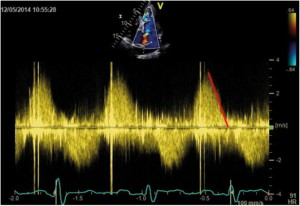

A 33-year-old man who had been diagnosed with PDA in childhood was refferedfor cardiac evaluation for fatigue and progressively worsening dyspnoea on exertion over the past 3 months. Physical examination revealed an afebrile patient, hyperdynamic precordium, a continuous murmur with thrill over the pulmonary area, peripheral oedema and hepatomegaly. The blood pressure was 120/60 mm Hg and the peripheral pulses were prominent. Auscultation of the lungs revealed mild basal crackles bilaterally. There were no clinical stigmata consistent with endocarditis. The ECG showed sinus rhythm at 78 bpm, biatrial abnormality, signs of left ventricular hypertrophy and complete right bundle branch block. There was no inflammatory syndrome or anemia. Transthoracic and transesophageal echocardiography confirmed the presence of a large PDA (defect size 11 mm), with a continuous systolic-diastolic flow signal with high velocities (up to 4.8 m/s) recorded by continuous wave Doppler examination at the level of this turbulent jet from the descending aorta to the pulmonary artery (Figures 1-3). The left ventricle was severely dilated (EDV/ESV=247/124 ml), with mild global systolic dysfunction (ejection fraction of 50%). The assessment of pulmonary artery systolic pressure was carried out by measuring peak tricuspid regurgitation velocity and the estimated value was 52 mm Hg. The TTE exam also revealed mobile vegetations on the pulmonary valve, with severe valve destructions, lack of coaptation and severe, free pulmonary regurgitation on color Doppler examination (Figures 4, 5). No vegetations were seen on the other valves, cardiac chambers or great vessels.

Figure 2. TTE examination, parasternal short-axis view; Spectral Doppler profile of continuous left-to-right ductal flow with high velocities (up to 4.8 m/s).

Figure 5. TTE examination, parasternal short-axis view. CW Doppler recording of pulmonary regurgitation showing a rapid flow deceleration during the diastole and increased systolic velocity (flow-related).